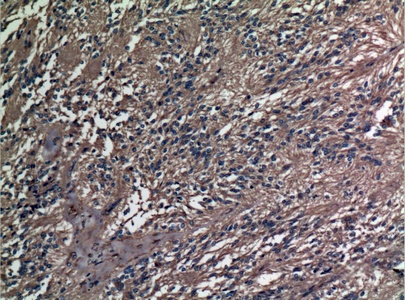

Immunohistochemical analysis of paraffin-embedded human-ovary, antibody was diluted at 1:100